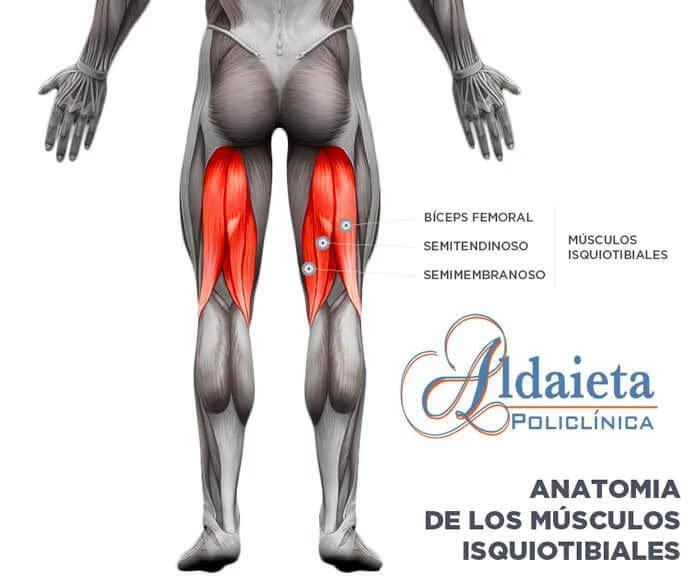

Anatomía y Función de los Isquiotibiales: Clave para el Movimiento

¿Qué son los isquiotibiales y por qué son tan importantes?

Los isquiotibiales son un grupo muscular potente y fundamental, situado en la parte posterior del muslo. Están compuestos por tres músculos principales: el bíceps femoral (con sus dos cabezas), el semitendinoso y el semimembranoso. Estos músculos se originan en la tuberosidad isquiática (parte inferior de la pelvis) y se insertan en la tibia y el peroné, justo debajo de la rodilla.

Su función principal es crucial para el movimiento humano y deportivo: son los principales encargados de la extensión de la cadera (llevar la pierna hacia atrás) y la flexión de la rodilla (doblar la pierna). Esto los convierte en protagonistas de actividades cotidianas como caminar, pero especialmente en movimientos explosivos y de alta demanda como correr, saltar, esprintar o patear. La correcta función de estos músculos es vital no solo para el rendimiento, sino también para la estabilidad de la rodilla y la prevención de lesiones en otras zonas. De hecho, cuando los isquiotibiales están débiles, acortados o desequilibrados, se incrementa el riesgo de sufrir lesiones no solo en el muslo, sino también en áreas adyacentes debido a compensaciones musculares y desequilibrios que pueden llevar a la amnesia glútea o problemas lumbares. Por lo tanto, la fuerza y flexibilidad de los isquiotibiales son indispensables para cualquier deportista.